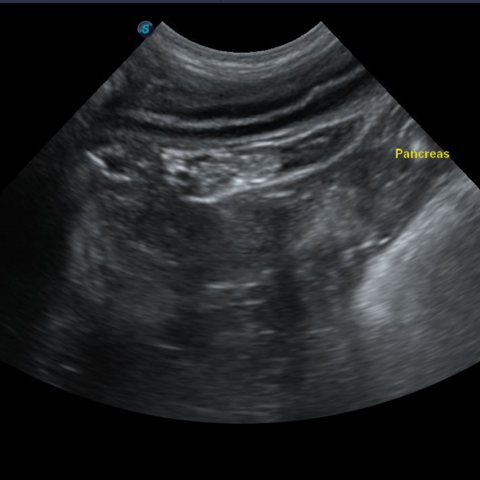

½ÄÀ̼º, Ư¹ß¼º, ¸é¿ª¼º ¿øÀÎÀ¸·Î »ý±â´Â ÃéÀå¿°Àº ±¸Åä, ¼³»ç, ½Ä¿åÀúÇϸ¦ ÀÏÀ¸Å°°í, º¹ÅëÀÌ ½ÉÇÑ Áúȯ ÀÔ´Ï´Ù. ´Ù¾çÇÑ ±âÀúÁúȯ¿¡ ÀÇÇØ ¹ß»ýÇÏ¿© ¸¸¼ºÈ µÇ¾î Àç¹ßÇÏ´Â °æ¿ì°¡ ¸¹¾Æ¼ ¸¸¼ºÀûÀÎ ÃéÀå¿° °ü¸®¿Í ÇÕº´Áõ °ü¸®°¡ ÇÊ¿äÇÕ´Ï´Ù.

ÃéÀå¿°